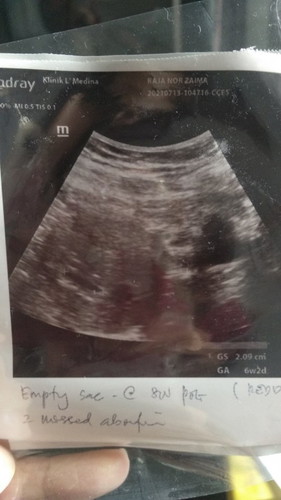

Kantung leper bila scan 8minggu.ada kemungkinan X dia Akan normal.doc dah cakap kandungan X menjadi.doc suruh cuci..tp saya nak tunggu dulu dlm 2minggu.harap Ada keajaiban.

Kantung leper ni Ada Cara X nak suruh dia bulat normal.saya ttc 4tahun dah.sangat down

kalau mcm ni mmg kena cuci sis.. mcm saya dlu.. pregnant kantung je.. cuba juga tunggu sampai 12 weeks.. tapi last2 kantung tu leper & terus bleeding.. kena cuci..

Kantung nmpk mcm dh ke bawah..